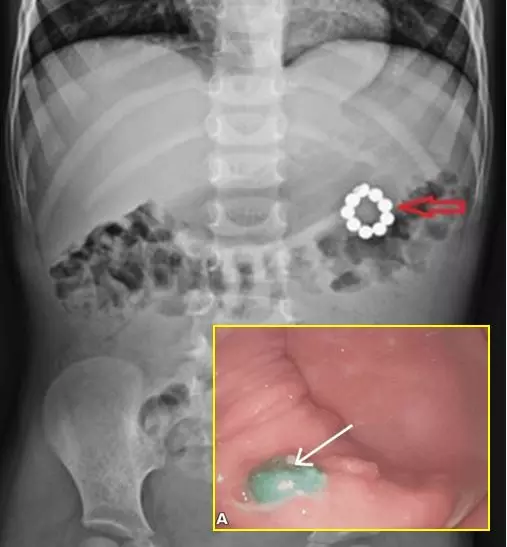

방글라데시 아스가르 알리 종합병원 의료진에 따르면 4세 남아는 3일간 지속된 복통과 메스꺼움으로 병원을 찾았다. 뚜렷한 다른 증상은 없었지만, 지난 두 달 동안 비슷한 증상으로 여러 차례 지역 병원을 방문한 이력이 있었다. 복부 진찰에서 상복부에 경미한 압통이 확인돼 엑스레이 검사를 시행한 결과, 복부 좌측 상단에 여러 개의 구형 이물질이 발견됐다. 정확한 섭취 시점은 확인되지 않았으나, 부모가 아이의 장난감 상자에서 유사한 구슬 모양 자석을 발견하면서 원인이 밝혀졌다.

의료진은 자석이 장을 가로질러 서로 달라붙으며 장벽을 관통하거나 고정됐을 가능성을 의심했다. 이에 따라 내시경과 외과적 수술을 동시에 대비한 치료가 계획됐다. 내시경 검사에서는 위 뒤쪽 벽에 여러 개의 자석이 박혀 있었고, 주변 조직에 궤양이 형성된 것이 확인됐다. 의료진은 내시경으로 5개의 자석을 제거했지만, 나머지 4개는 위벽에 깊이 박혀 있어 제거가 어려웠다.